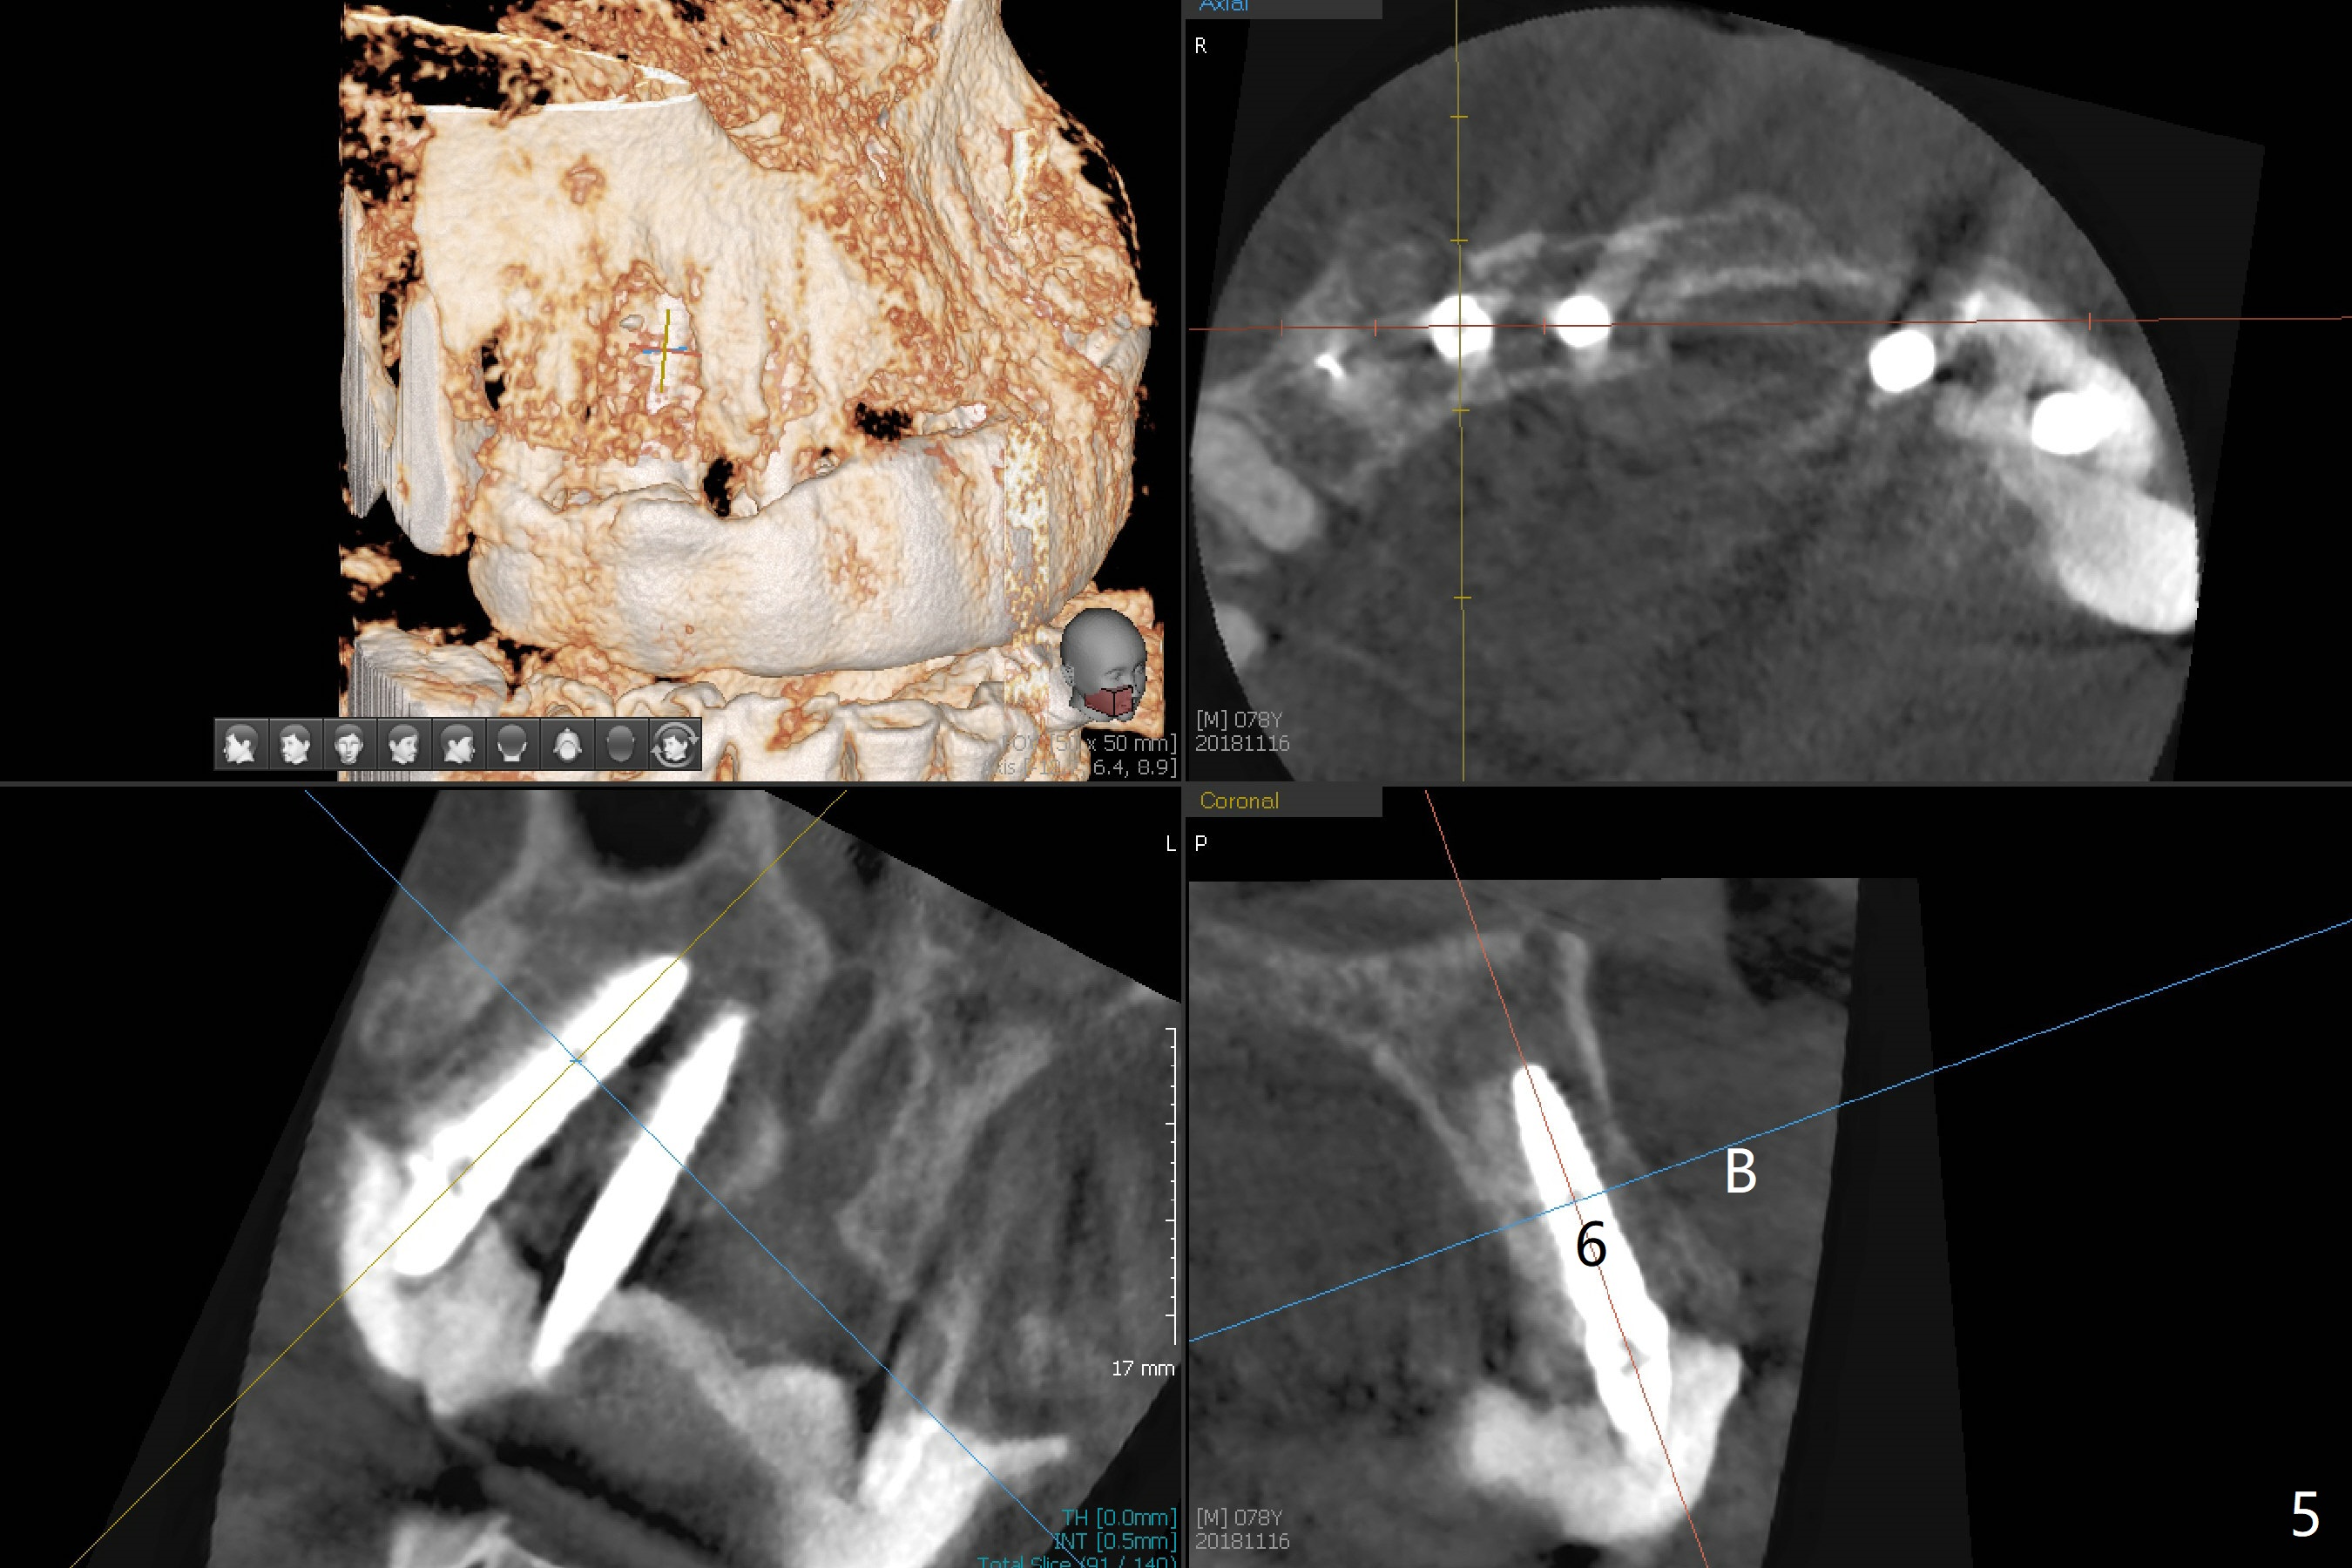

It is smooth and quick to finish osteotomy with guide at #6,7,10-12, but when 3 mm 1-piece implants are placed free hand at #7 and 10 (Fig.1,2), the gingival parts of the abutments contact the incisal edges of the lower incisors (anterior deep bite) in spite of effort to change the trajectory by repeated back and forth placement after use of Lindamann bur buccally. Following an immediate provisional (Fig.3,4), the occlusal surface of the posterior teeth are raised to eliminate anterior restoration interference. Immediate postop CBCT shows that the implants at #7 and 10 could be placed more buccally (Fig.6,7, as compared to the normal position at #6,11,12 (Fig.5,8,9)). Fig.10 was taken 2 days preop, while Fig.11-13 postop. Can we change 1-piece implants (3mm) at #7 and 10 to 2-piece one (3.5) and use angled or cementation abutments for easy restoration (Fig.14-16)?